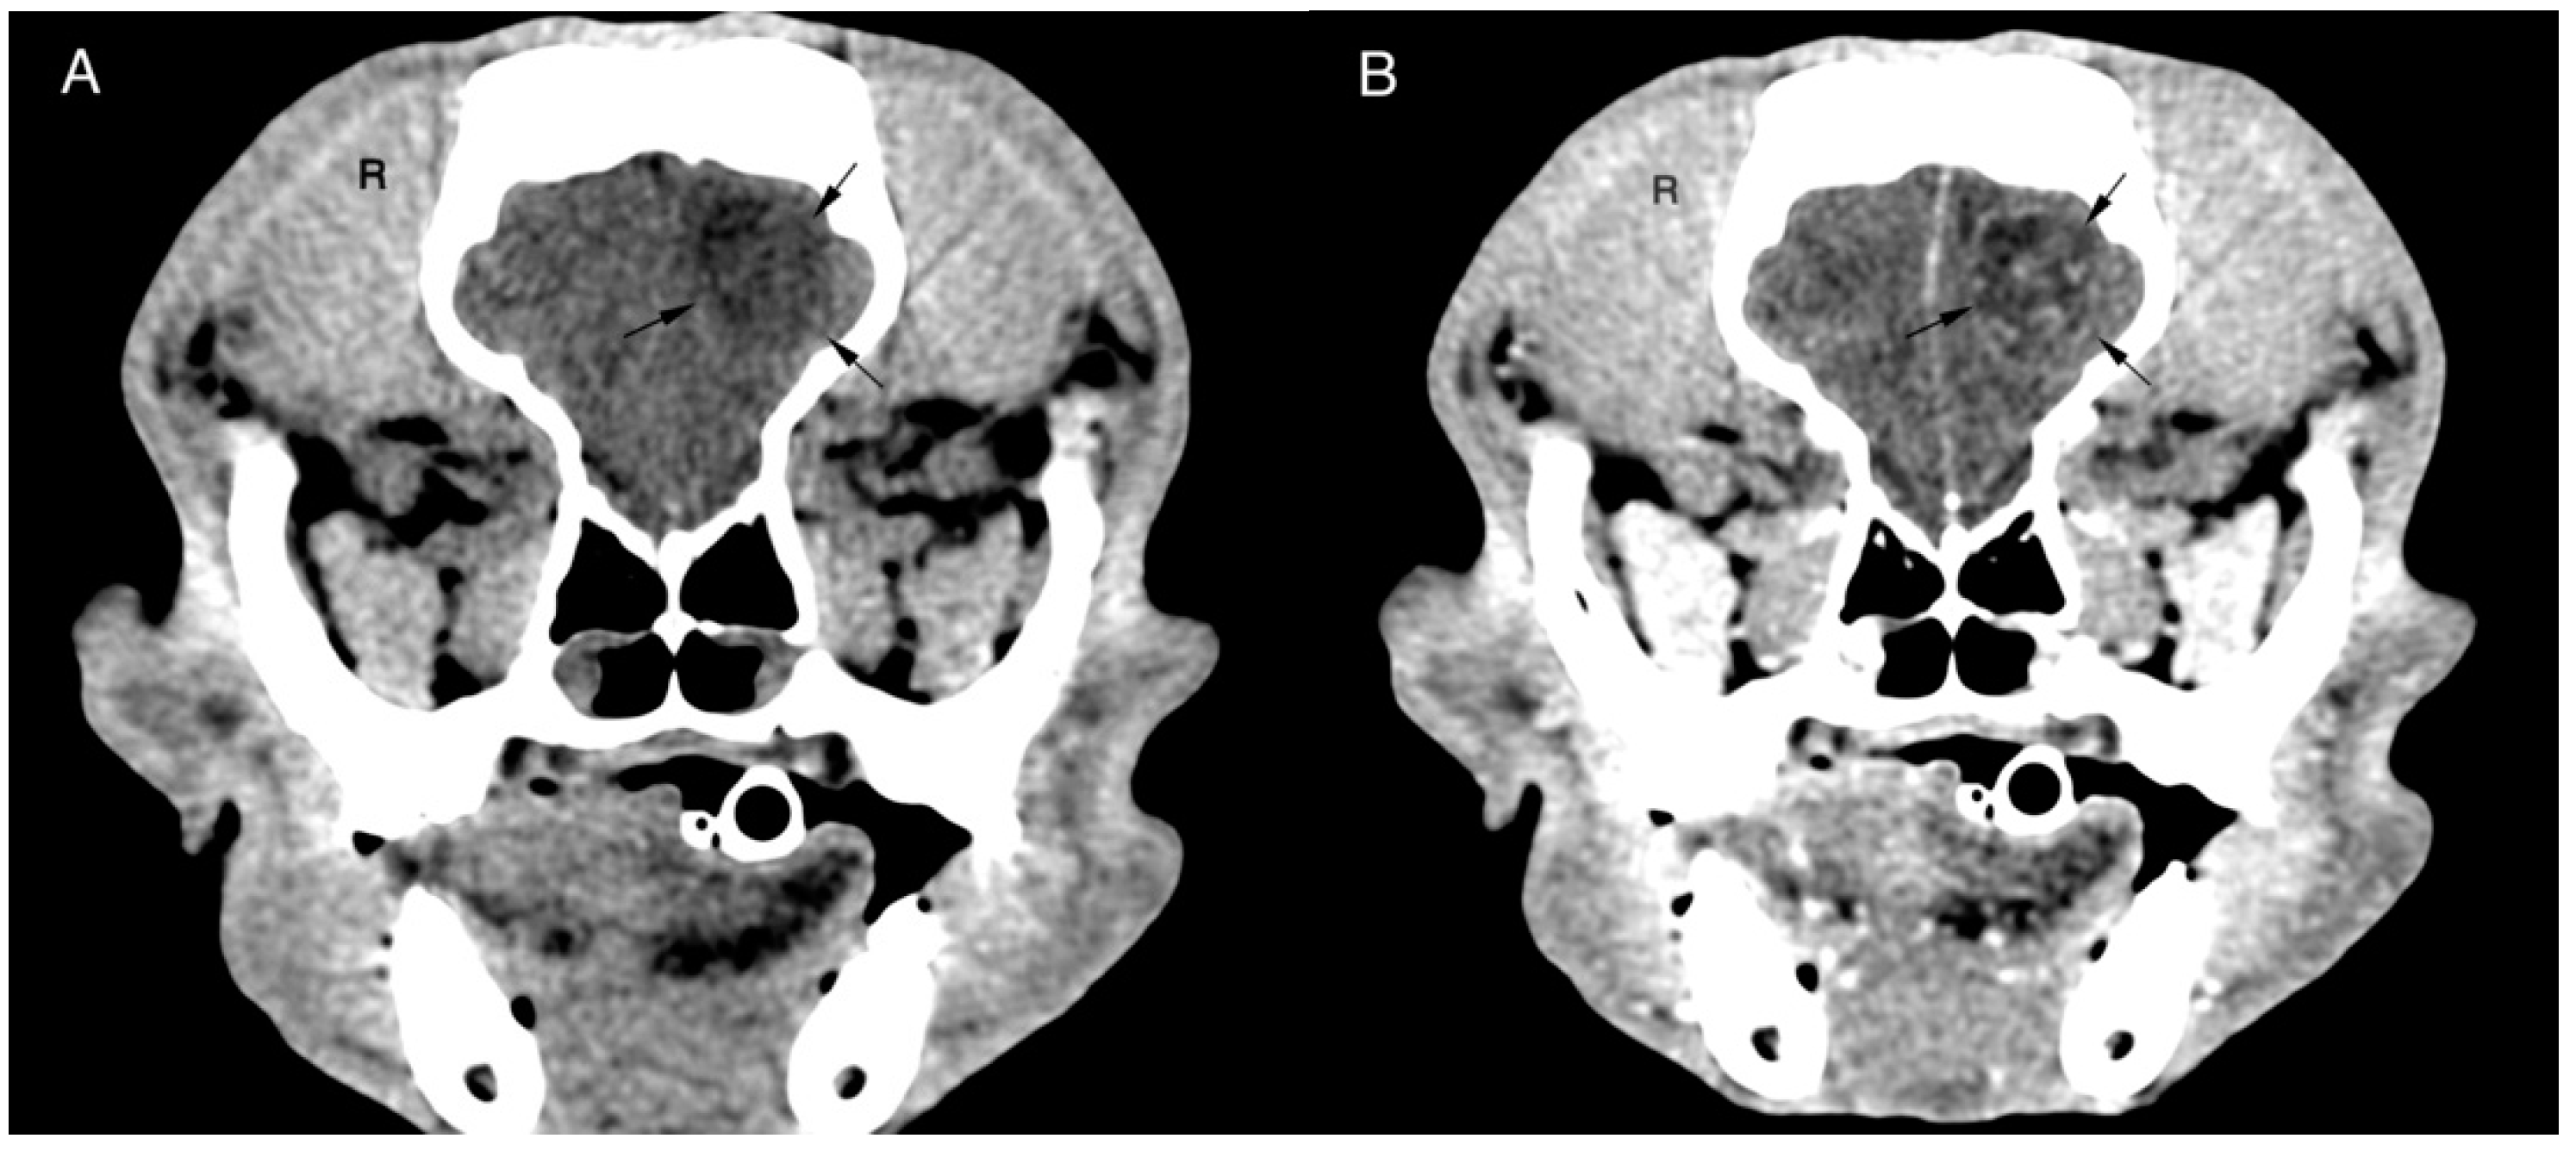

| English Bulldog | F | Y | 4 | 25.5 | Obtundedmental status | Right circling, left proprioceptive deficits, decreased menace response OS | Left cerebellum | 1 | Anaplastic oligodendroglioma grade III | 1st Temozolomide (160.9 mg/m2 for 5 days every 3 weeks) | CT confirmed | 120 | Euthanasia due to tumour regrowth |

| French Bulldog | M | N | 5 | 13.3 | Seizures | Mild right proprioceptive deficits and decreased menace response OD | Left frontal lobe | 1 | Oligodendroglioma grade II | 1st Temozolomide 181.8 mg/m2 for 5 days every 3 weeks) 2nd Lomustine (70 mg/m2 every 3 weeks) | CT confirmed | 240 | Euthanasia due to tumour regrowth |